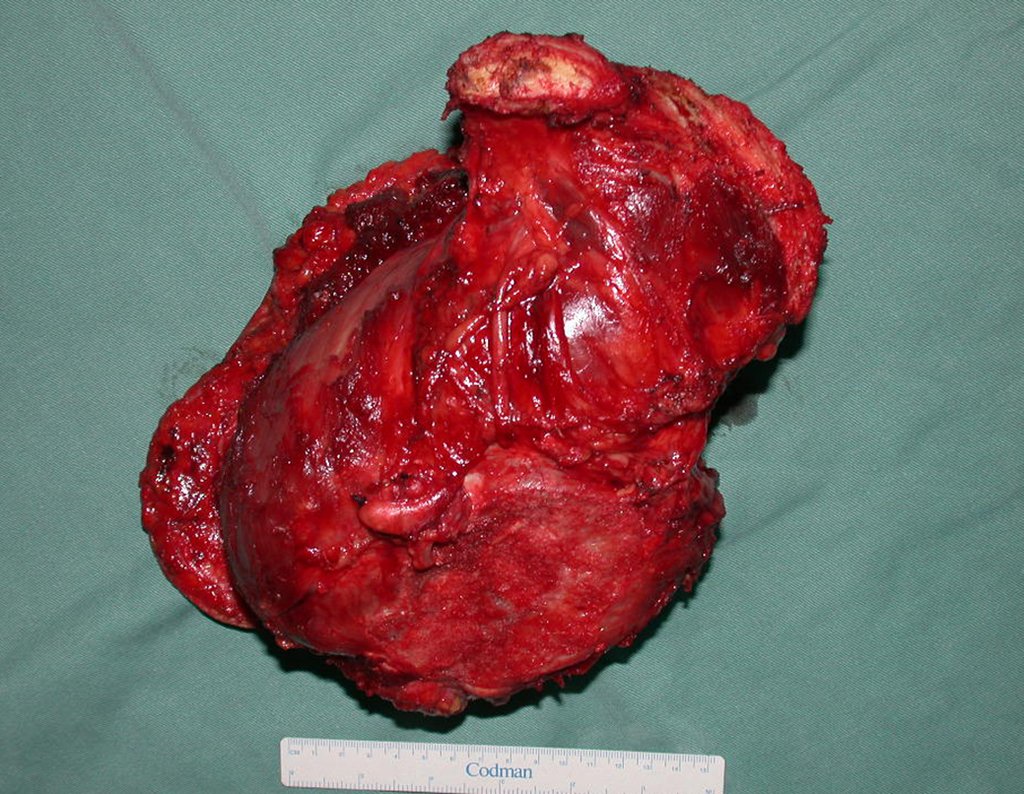

A paciente foi submetida a uma pelvectomia interna total para ressecção do condrossarcoma. O procedimento foi realizado com cuidado para garantir margens de segurança e minimizar o risco de recidiva.

- Ressecção em bloco da hemipelve esquerda e revisão da hemostasia.

Imediatamente após a cirurgia, radiografias confirmaram a ressecção completa da hemipelve esquerda, juntamente com o colo femoral e o complexo capsulo-ligamentar da articulação do quadril esquerdo.